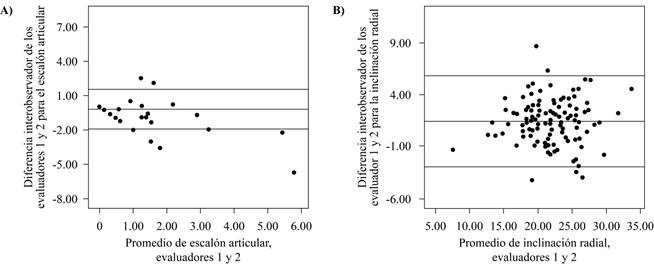

La Figura 2 ejemplifica la reproducibilidad entre el promedio de las dos mediciones hechas por los evaluadores 1 y 2 en el escalón articular y la inclinación radial. Se muestran los promedios de las mediciones hechas por los evaluadores en el eje horizontal y las diferencias de las medidas de los evaluadores en el eje vertical. Las líneas superior e inferior representan los límites a ± 2 DE y la línea central la media de las diferencias. El escalón articular (a) presentó un rango de 3.46 mm a ± 2 DE con un porcentaje de medidas fuera de los límites de 7.2%. En la inclinación radial (b) el rango fue de 8.86º y el porcentaje fuera de límites de 4.5%.

Figura 2: Gráficos de Bland-Altman ilustrando la reproducibilidad interobservador de los promedios de las dos mediciones del evaluador 1 y 2 para el escalón articular A) y la inclinación radial B); las líneas centrales representan la media de las diferencias entre los evaluadores, y las líneas superiores e inferiores los límites a ± 2 desviaciones estándar de la media.